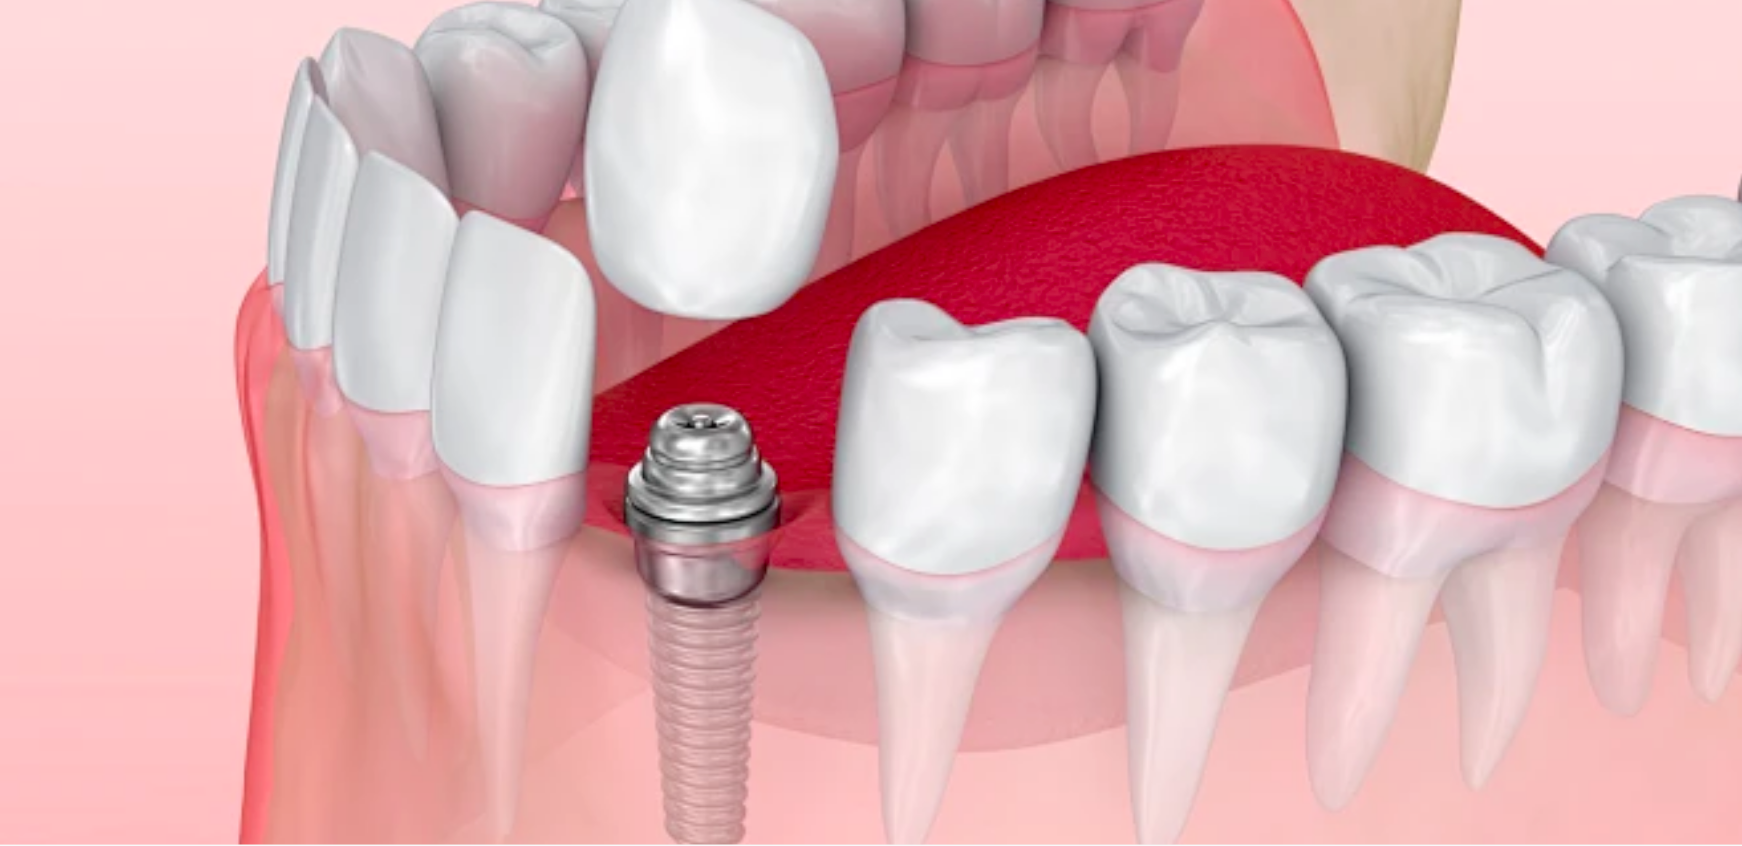

口腔种植学科

DENTAL IMPLANTATION

兔博士口腔医疗科技集团口腔种植学科,专业种植设备辅助,可以有效保障牙齿种植质量。采用世界知名品牌种植体,每颗植体都有自己的“身份证”,且都经过国家药监局备案。

面对复杂的口腔种植案例,兔博士口腔医疗科技集团有完善的会诊机制,确保种牙方案科学合理。除此外,集团率先提出种牙维养服务,通过定期维养,延长种植牙的使用寿命。

牙齿种植

DENTAL IMPLANT

种植牙是指在缺牙的地方种植上高科技处理的纯钛金的牙根后,在上面镶复烤瓷牙或全瓷牙,恢复牙齿咀嚼功能的牙齿缺损的修复方法。

其原理是在缺失牙的部位将纯钛的种植体植入牙床内,3个月后,种植体通过表面的生物活性涂层与周围骨质发生骨融合,然后在种植体上安装牙冠或牙桥;